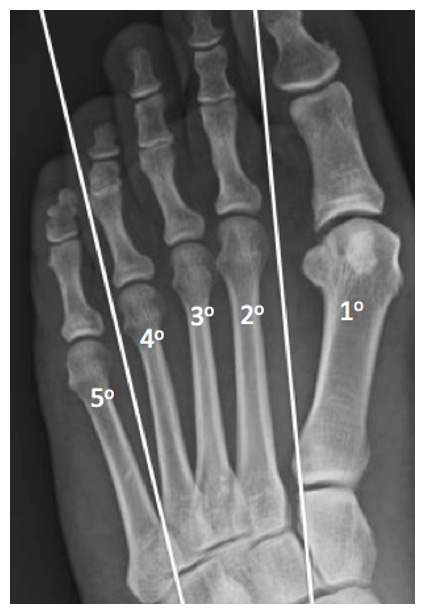

O tão conhecido Joanete, nome popular do hálux valgo, caracteriza-se por uma saliência na região medial da base do dedo grande (hálux), anatomicamente descrita como articulação metatarsofalângica. O aparecimento deste volume ocorre devido a um desalinhamento ósseo, e não pela formação ou surgimento de osso novo, como muitas pessoas pensam. Além disso, outras deformidades, como dedos em garra, pé plano ou outras alterações, podem estar associadas.